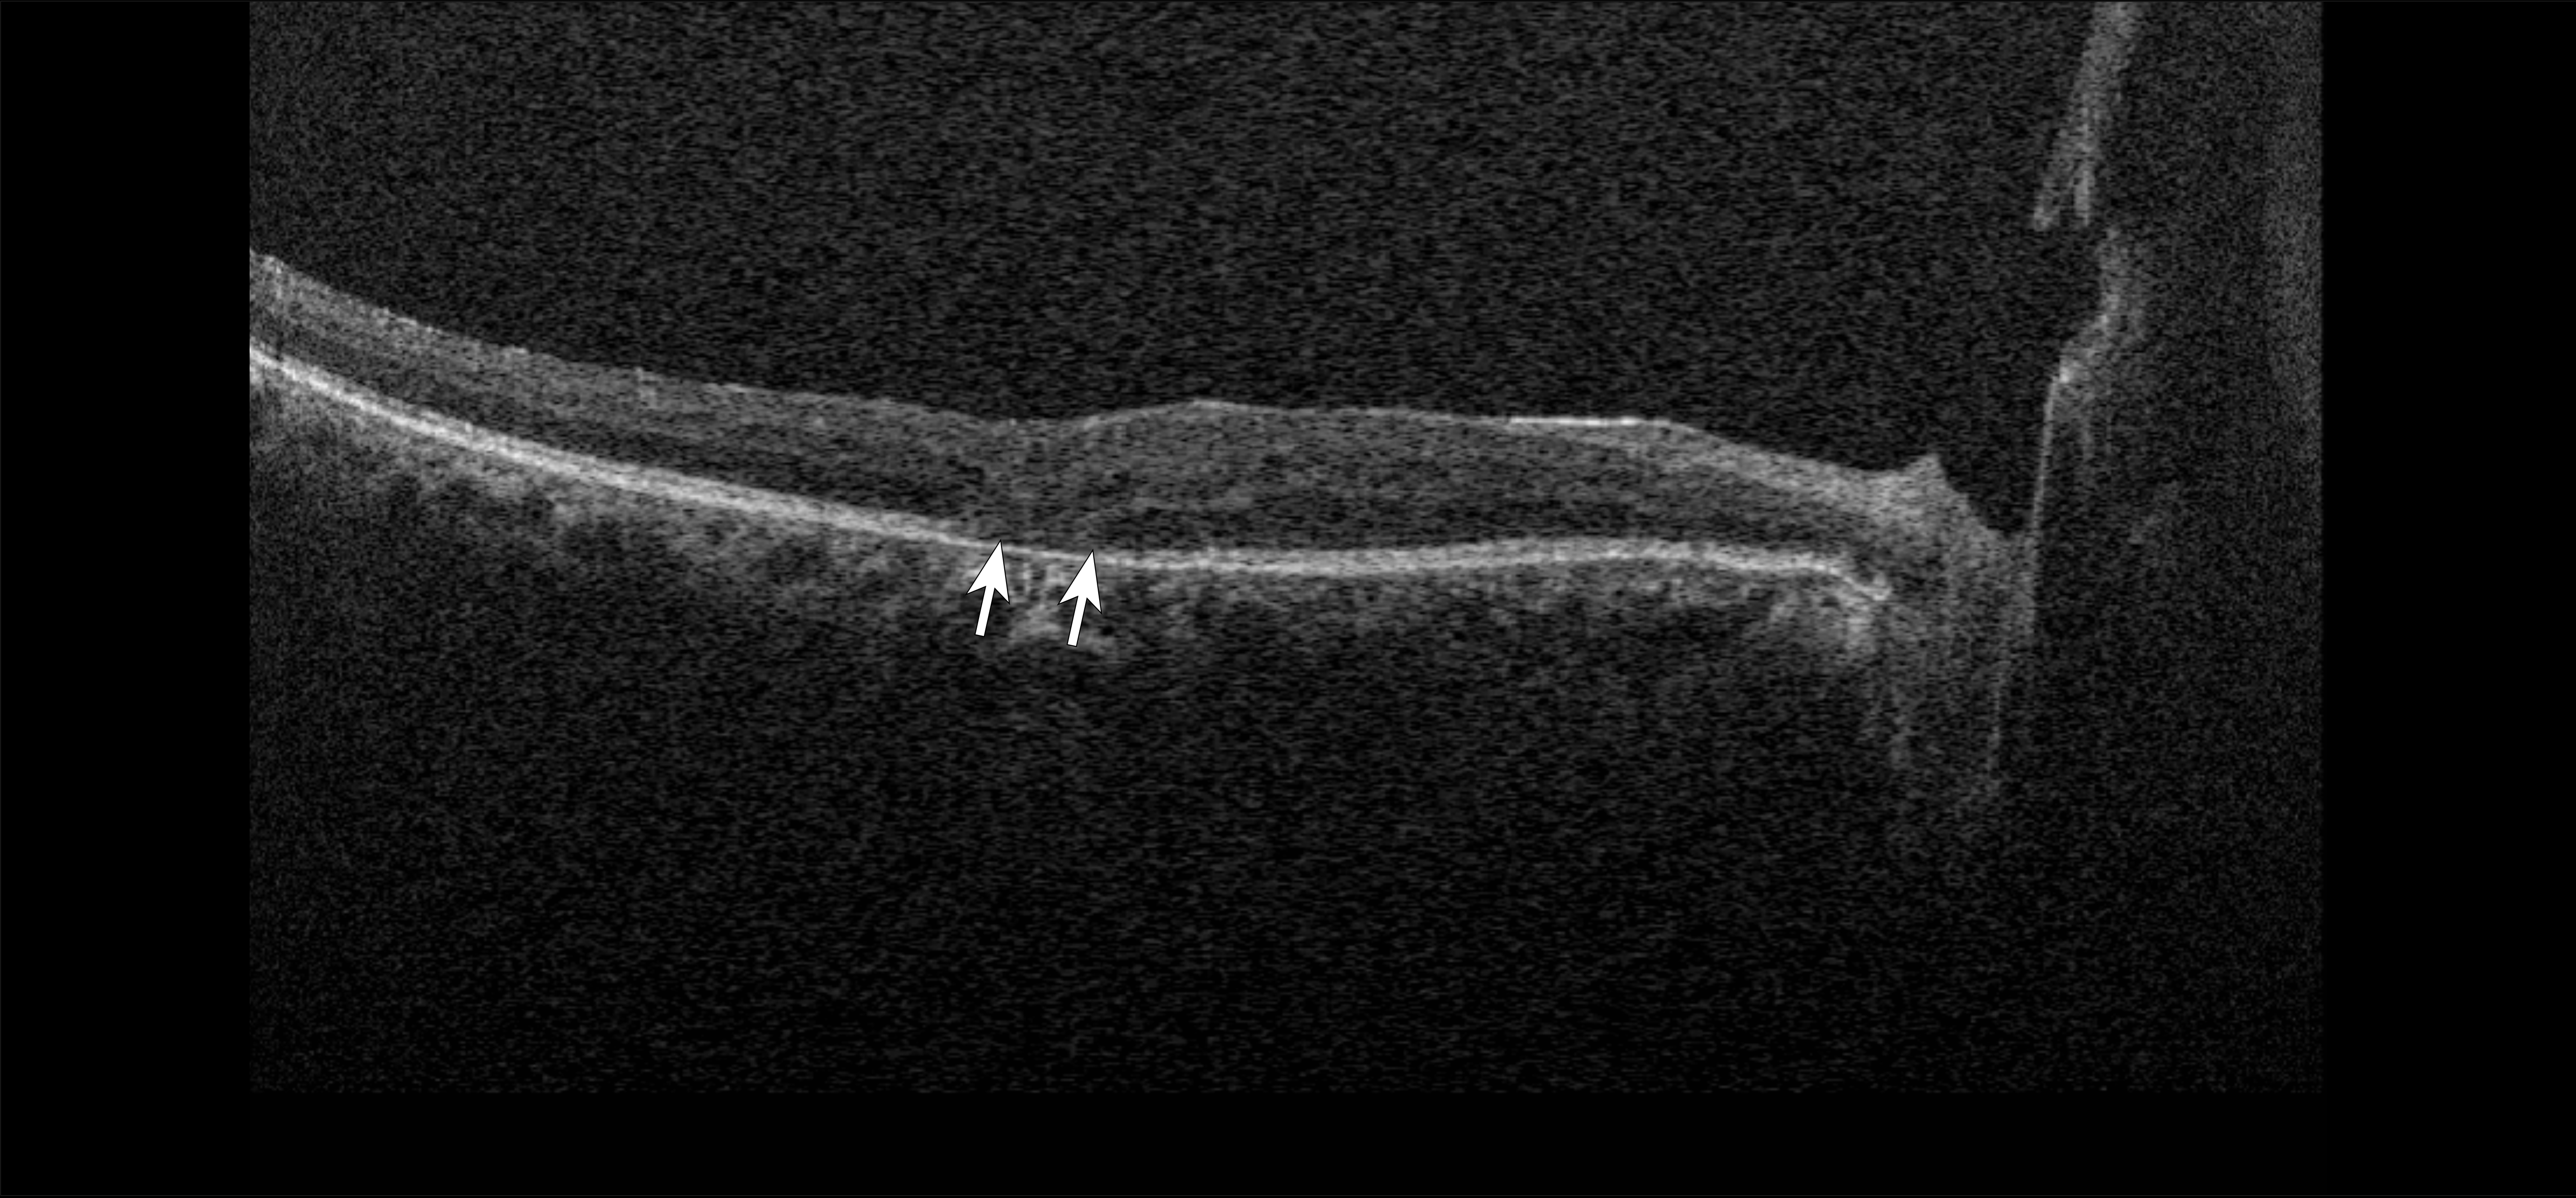

| Figure 2. Optical coherence tomography of a 59-year-old with a history of proliferative diabetic retinopathy demonstrating outer retinal disruption (arrows). |

More specific pathologic changes such as disorganization of the retinal inner layers (DRIL; Figure 1) can be appreciated only through OCT and have been identified as markers of visual potential and predictors of DR progression.4 Similarly, outer retinal disruption (Figure 2) and early photoreceptor damage may indicate more advanced disease with poor visual prognosis.5